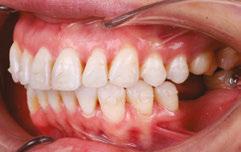

Patient S.T., age 32, presented in the hope of creating a radiant smile and a functional bite. She had been dealing with dental problems all her life. Her X-rays exhibited multiple direct restorations as well as endodontic treatment. Due to the loss of her molars, her teeth had shifted considerably over the years. Her dentist recommended she see us to create a pleasing smile and to rehabilitate her occlusion for future prosthetic treatment (Figure 8).

Diagnosis

The patient’s occlusion was super CL I on the left and CL II on the right. Both arches showed slight constriction with lower anterior crowding. Her smile arc was canted, and both midlines were shifted in opposite directions. On cephalometric

Figure 7: Case 1 progress to date — 4 months (left) and 10 months (right)

Figure 8: Case 2 initial records

development, arch coordination, and mandibular labial crown torque control. Note how well her tissue responded to the slow, gradual changes with no gingival recession. This is simplicity.

Case discussion

analysis, her ANB was 5.84, and IMPA was 102.64, both representative of skeletal Class II with incisor proclination. There were two long-standing extraction sites into which the UR6 and UL6 (partial) had supraerupted. Her thin gingival mucosa posed a challenge in keeping the roots in the bone, so treatment had to be planned correctly and executed gradually to maintain her gingival architecture.

Treatment plan

Use Angel Aligner to sequentially distalize the UR and LL quadrants, correcting the AP relationship and obtaining midline coincidence (Figure 9). Intrude the supraerupted U6s to prepare the extraction sites below for implants. To preclude root resorption and fenestrations, careful attention would be paid to tooth movement velocity and the sequencing of those movements.

In the past, I would have used fixed appliances and TADs to treat this patient. I considered adding a TAD in the IZC area to intrude the supraerupted UR6, but I wanted to see what Angel Aligner alone could achieve.

Case progression

At 4 months, the maxillary right side had distalized with appreciable space created between the canine and first premolar (Figure 10). At 9 months, this patient has a wide, attractive smile emerging (Figure 11). We can also appreciate the transverse

This patient’s multiple dental and occlusal issues were resolved solely with Angel Aligner. Both U6s were intruded without needing TAD support or additional mechanics to preclude labial crown torquing. Angel Aligner proved more than adequate in displacing the UR6 vertically while simultaneously distalizing it into Class I (Figure 11). To be able to intrude and distalize simultaneously with no need for TAD-supported anchorage speaks to the exceptional capability of this appliance.